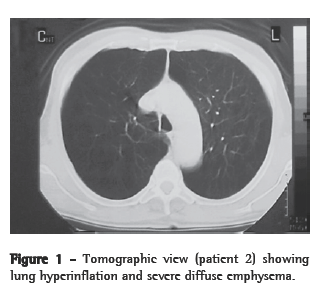

Bleomycin or saline was administered 3 days after the beginning of quercetin or vehicle treatment (Figure 1). The treatments were continued for an additional 14 days after intratracheal instillation, at which time the hamsters were killed.